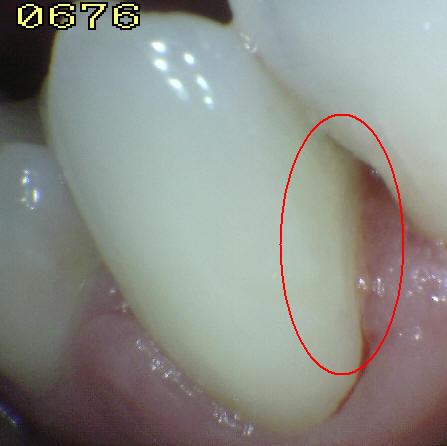

Código 4

(Caries Moderada): Sombra oscura

de dentina subyacente al esmalte intacto con o sin interrupción

localizada del esmalte

-

Esta lesión aparece como una sombra de decoloración

visible a través de una superficie de esmalte intacta, la que puede o no mostrar signos

de descomposición localizada del esmalte, como la microcavidad y /o discontinuida

< 0,5mm. después del secado con aire durante 5

segundos

-

La aparición de

la sombra se ve a menudo con más facilidad cuando

el diente está húmedo. El área oscura es una

sombra intrínseca que puede aparecer gris, negro-azul o

marrón-anaranjado,

a través de las paredes del esmalte vestibular, lingual o

palatino